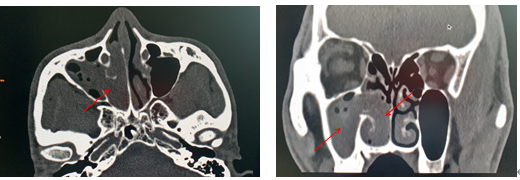

患者李某,男性,42岁,于4月前无明显诱因出现右侧鼻塞,流清涕、打喷嚏,伴咽干咽痛、口干口苦。入院前2天曾在当地医院检查发现右侧鼻腔肿物,建议手术治疗。患者随后在我院耳鼻喉科就诊,收治入院后查副鼻窦CT提示:右侧鼻道内软组织密度块影,病变累及鼻咽部、右侧上颌窦及右半筛窦。进一步完善副鼻窦核磁平扫+增强+DWI提示:右侧鼻腔内异常信号并向鼻咽腔及右侧上颌窦腔内延伸,结合强化,多考虑肿瘤性病变,内翻性乳头状瘤可能。术前病检回报示:(右侧鼻腔)内翻性乳头状瘤。诊断明确后,由科主任江燕主刀、在麻醉手术科主任医师谭萍的全力配合下,耳鼻喉科团队为患者成功施行全麻下“鼻内窥镜下右侧鼻腔鼻窦肿瘤切除+右侧上颌窦开放术”,术中完整切除患者右侧鼻腔鼻窦肿瘤,术后恢复良好。

术前副鼻窦CT提示右侧鼻腔、鼻咽部及上颌窦内肿物